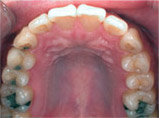

齒列擁擠的不正咬合經由擴大效果排列整齊:

Before

Proceeding

After